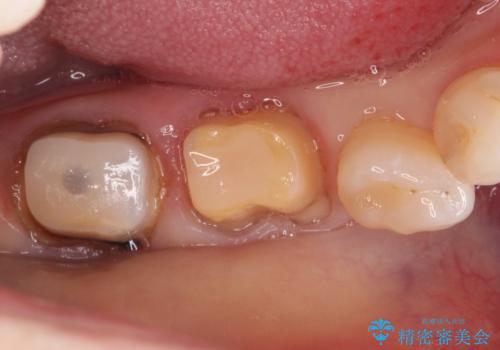

- 他院で治療した被せ物が取れたを主訴に来院された患者様です。被せものが外れた隣の歯もプラスチックの詰め物の劣化や歯に亀裂があったためオールセラミッククランで治療を行いました。

昔詰めたプラスチックの詰め物の範囲が大きいのと破折のリスクや強度の担保のためインレーではなくクラウンで治療を行いました。